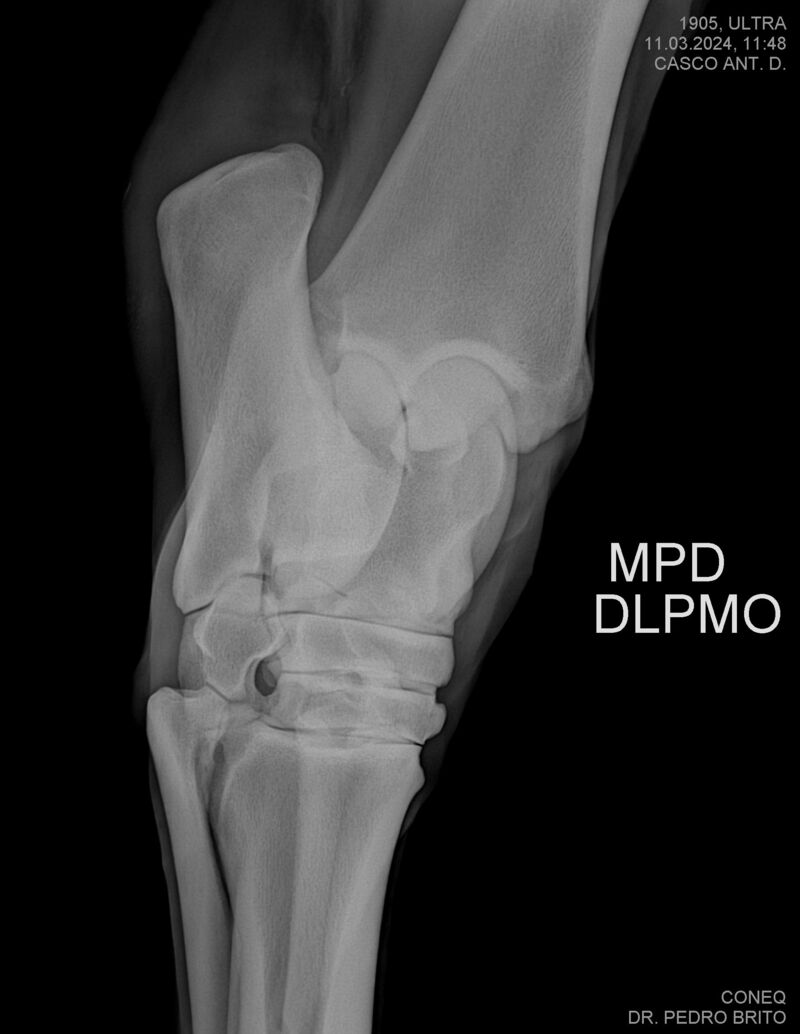

ULTRA DO CACH